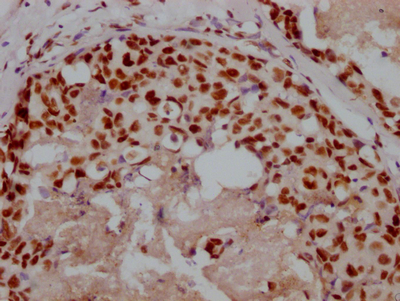

The image on the left is immunohistochemistry of paraffin-embedded Human thyroid cancer tissue using CSB-PA985822(ATP2A3 Antibody) at dilution 1/30, on the right is treated with synthetic peptide. (Original magnification: ×200)